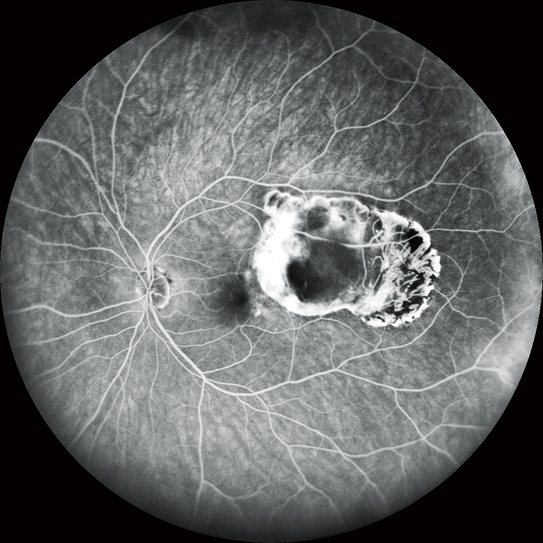

高清動態血管造影

可錄制分辨率高達1,024 x 1,024像素,最長時長為120秒的視頻。在同一次測量中也可分段錄制多個短視頻。

FA和ICG同步血管造影

Mirante操作簡便,可同步拍攝FA和ICG影像。實時IR監測方便操作者在熒光產生前調整拍攝位置,降低錯過血管造影早期階段的風險。

自動增益控制(AGC)可同步調整各個FA和ICG圖像的對比度,使動態血流成像成為一個非常簡便的過程。

* 適用于SLO/OCT型。SLO型可選。

同步FA和ICG成像顯示

實時紅外監控